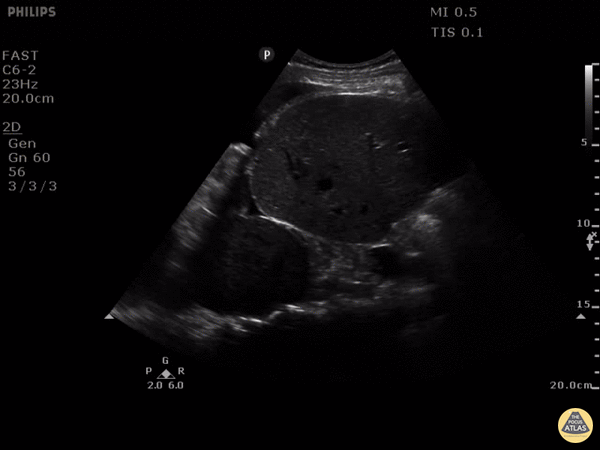

PLEURAL EFFUSION, THE SPINE SIGN AND SOMETHING ELSE… This is a clip of a 46 year old woman that presented to ED with gradual onset of severe right-sided chest pain, pleuritic, associated with tachycardia but normal blood pressure. She was mildly tachypneic but not hypoxic, unable to lie down as that exacerbated her pain. The clip shown here is of the patient's right upper quadrant and right lung base. The spine sign is seen along with a right pleural effusion and a circumscribed mass 8 x 6 cm with likely compressive atelectasis and mass effect of the right hemidiaphragm. The effusion was drained obtaining almost 1L of blood, and the CT scan reported very close findings to the ones seen with POCUS a few seconds after patient arrival. Put the probe on your chest pain patients! Maria Perez; Emergency Registrar; St Vincent’s Hospital; Melbourne - Australia